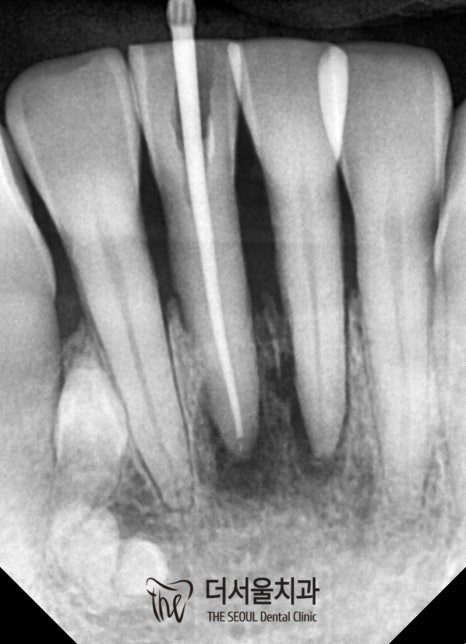

재신경치료를 통해 감염된 곳을

꼼꼼히 제거한 뒤 수복재를 사용하여

빈 곳이 없도록 꽉꽉 채워 넣었습니다.

이후 밀폐까지 확실하게 마쳤는데요.

그러나 여기서 끝이 아니라는 점.

염증의 크기가 작아지긴 했지만,

사라진 것은 아니기 때문에

꾸준한 관찰을 통해 병소가 사라졌는지

확실하게 확인을 해야 됩니다.